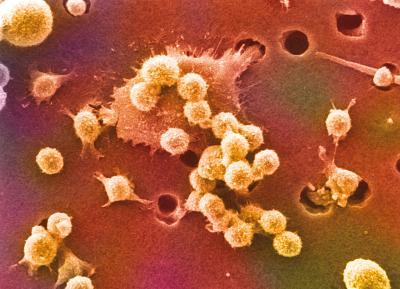

Cosa sono le sindromi linfoproliferative Le patologie linfoproliferative sono un gruppo secondario di patologie che interessano gli organi linfoidi secondari; il primo gruppo sono i linfomi Hodgkin e Non-Hodgkin. Principali sindromi linfoproliferative Le principali...

Che cos’è la leucemia acuta Le leucemie sono un gruppo eterogeneo di neoplasie che originano dalla trasformazione neoplastica di cellule emopoietiche. La cellula bersaglio della trasformazione leucemica può essere rappresentata dalla cellula staminale pluripotente...